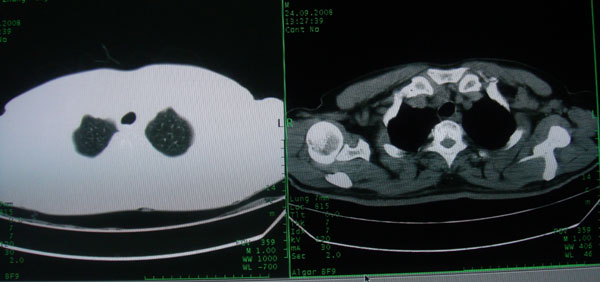

患者男性58岁因二周前起咳嗽,今天胸片示左上肺占位性病变行ct检查,无发热,无咯血痰.

左肺上叶病灶,实变但见含气支气管、空洞但未见壁内结节及积液;

初学者。。。左肺空洞性病变,并可见阻塞性肺不张改变,鉴于患者为老年男性,且临床症状仅有咳嗽,全身中毒症状不明显,所以我首先考虑为左肺癌性空洞并左侧肺门淋巴结转移伴左肺阻塞性肺不张。结核性空洞放于第二位考虑,可以进行相关实验室检查。希望能有病理结果,谢谢!!!!!

左肺上叶实变影,内见支气管充气征及空洞影,病人年龄较大,无发热及结核中毒症状,心影左移,未见纵隔淋巴结肿大;不知实验室检查结果如何?有否嗜酸细胞增多,有没有进行治疗?就目前资料首先考虑1.感染性病变,2.慢性嗜酸性肺炎?可结合实验室检查并短期治疗复查,肺癌不能排除。